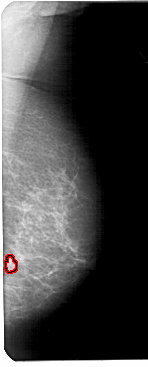

FILE: A_1600_1.RIGHT_MLO.OVERLAY

TOTAL_ABNORMALITIES 1

ABNORMALITY 1

LESION_TYPE MASS SHAPE FOCAL_ASYMMETRIC_DENSITY MARGINS ILL_DEFINED

ASSESSMENT 4

SUBTLETY 1

PATHOLOGY BENIGN

TOTAL_OUTLINES 1

BOUNDARY